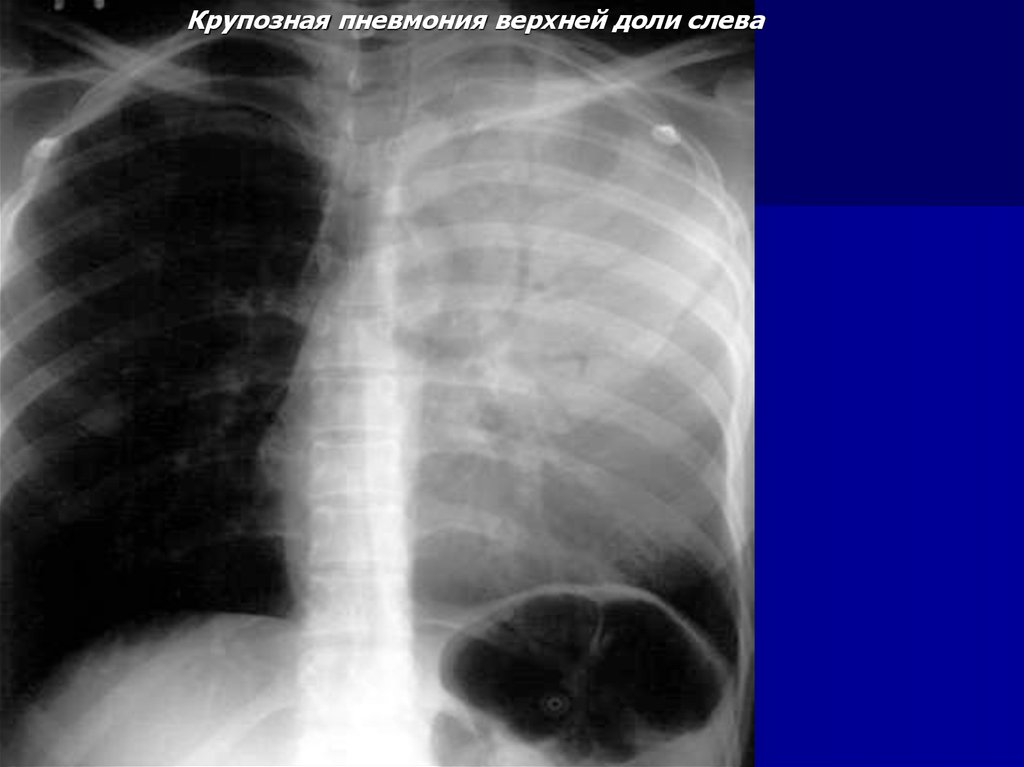

Крупозная пневмония верхней доли слева